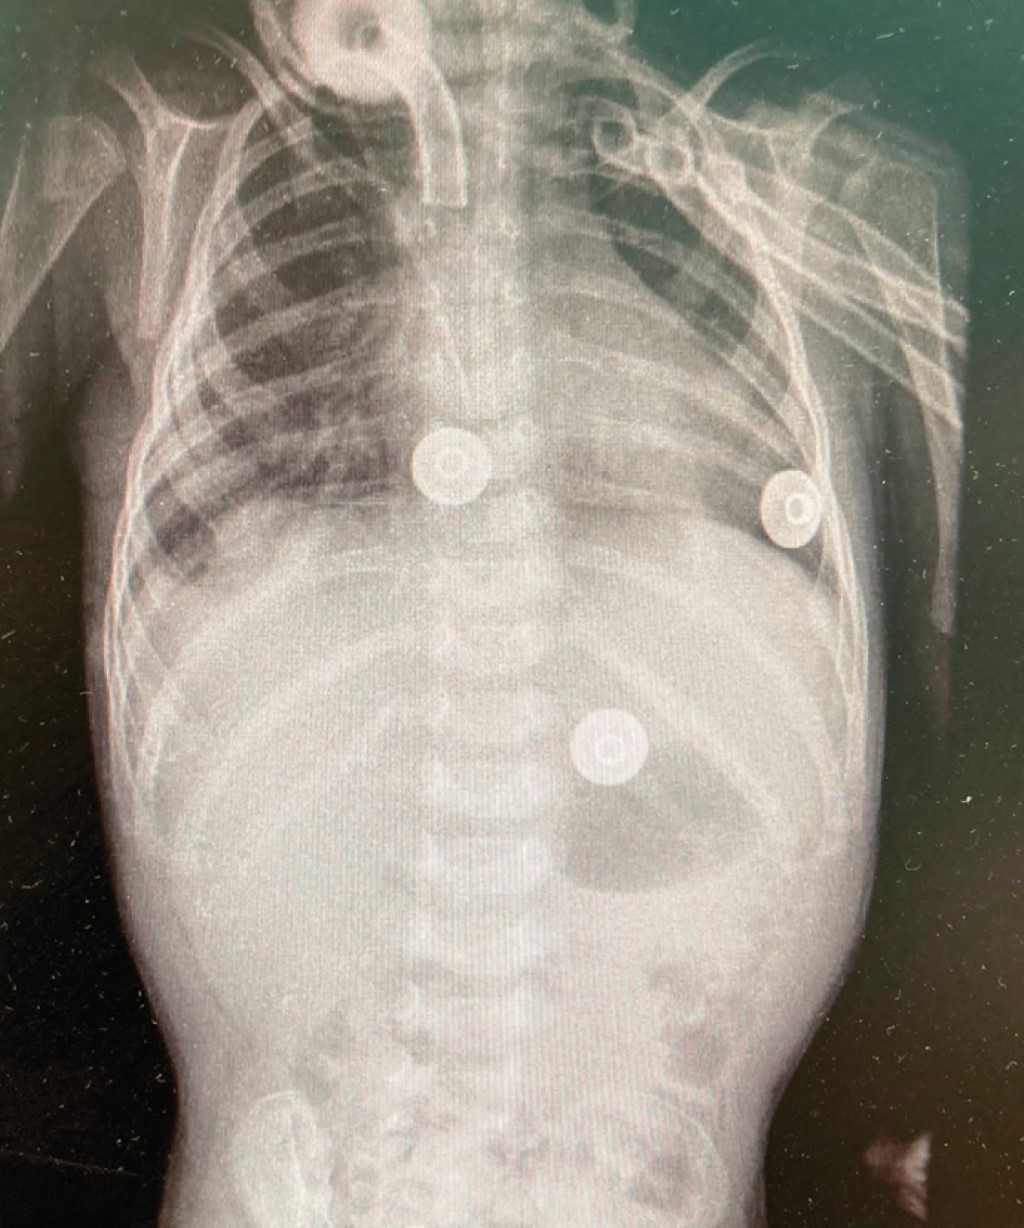

Inició su padecimiento actual aproximadamente tres horas previas a su ingreso, con emesis de contenido gástrico, cianosis central durante dichos eventos y tos productiva en accesos, por lo que acudió de manera inicial con facultativo de primer contacto, quien descarta patología respiratoria considerando probable cardiopatía congénita, por lo que refiere paciente a hospital de segundo nivel de atención para protocolo de estudio. A su ingreso al Servicio de Urgencias, se encontró irritable, con cianosis central y datos de dificultad respiratoria con saturación por oximetría de pulso de 85%, mejoró con oxígeno con cámara cefálica, ruidos cardiacos rítmicos con adecuada intensidad y frecuencia sin agregados. Se realizó estudio radiológico toracoabdominal en donde se observó aparente cardiomegalia y puesto que requería oxígeno con cámara cefálica a 3 litros por minuto se ingresó al Servicio de Pediatría con diagnóstico de cardiopatía congénita en estudio, de modo que se descartó en el momento un proceso infeccioso. Fue valorado por cardiopediatría quien descartó patología a este nivel con evolución clínica tórpida ya que persistieron los datos de dificultad respiratoria, así como la disminución de la saturación de oxígeno, requiriendo estancia en la Unidad de Cuidados Intensivos Pediátricos con fase III de ventilación, se tomó nuevo estudio de imagen en donde se observó elevación anormal del hemidiafragma derecho (Figura 1), por lo que se solicitó interconsulta al Servicio de Cirugía Pediátrica, con la sospecha de tener una patología diafragmática.

Figura 1